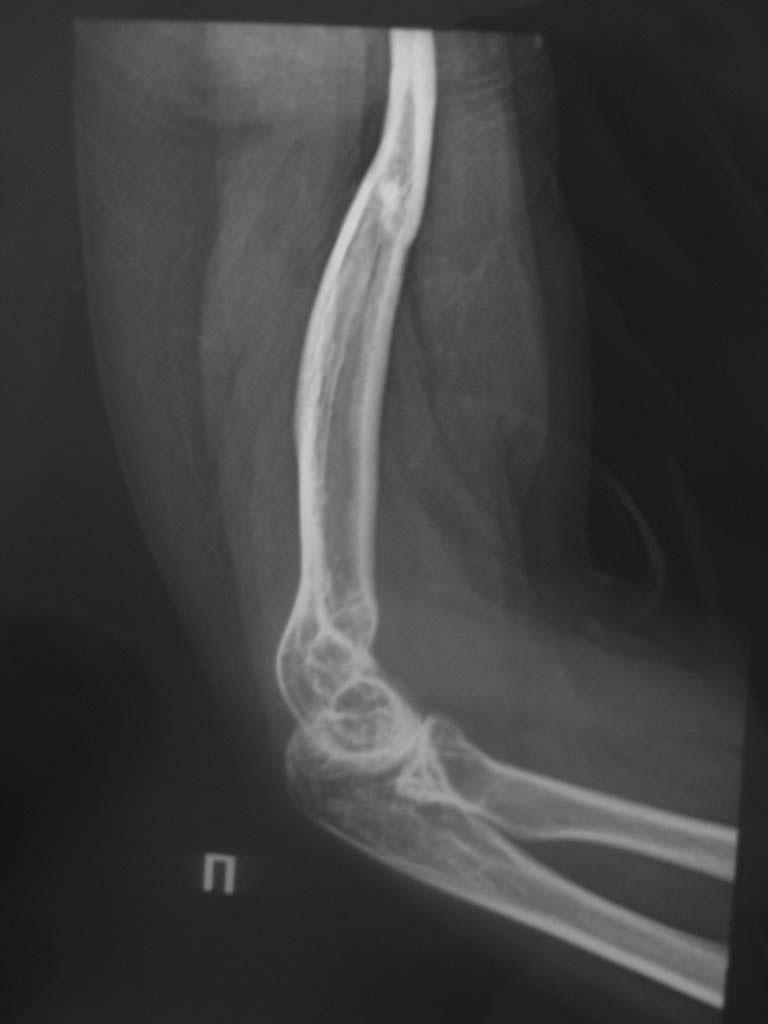

Игорь Владимирович . Пишу подробно. Больная травму получила в детстве (в 1996г) . Через год после травмы было подозрение на опухоль головки плеча (со слов больной), оперирована - резекция опухоли, артродез правого плечевого сустава с перемещением аутотрансплантата из малоберцовой кости. Послеоперационный период спокойный. Со слов больной, артродез состоялся. Года 3 назад почувствовала боль. (ударилась). В настоящее время движений в плечевом сустава нет. В локтевом и лучезапястном суставах движения не ограничены, в полном объеме. Функция предплечья в норме. Выложу рентгеновские снимки локтевого сустава. Спасибо за совет.

По представленным рентгенограммам судить о "былом артродезе" очень тяжело, а точнее даже сомнительно.

Во всем этом очень смущает состояние проксимального конца плечевой кости. Весьма сомнительно, что несколько лет после перелома в области артродеза могли привести к таким изменениям и я поддерживаю сомнение доктора Челнокова - а был ли артродез?

По моему мнению лучше туда не лезть, судя по состоянию костной ткани оперативное лечение ни к чему хорошему не приведет. Дополнительная травматизация сосудов питане кости не улучшит. Если пофантазировать, какой нибудь онкологический протез (как на т/бедренном или коленном суставе) может быть и можно было установить. А так, артродезом там и не пахло. Скорее всего на рубцах было что то вроде анкилоза, и во время травмы все это расшаталось. Я бы порекомендовал ношение плечевого ортеза 4 недели.

Если исключить как возможную зону имплантации эндопротеза - свободный трансплантат малоберцовой кости, то остается нижняя треть плеча. Длина костно-мозгового канала слишком мала. Кроме того, если пациентке в детском (16 лет назад) возрасте был выполнен артродез (даже если костный анкилоз не состоялся), мышечная система плечевого пояса адаптирована скорее для использования конечности именно таким образом. Пользоваться адекватно эндопротезом она вряд ли сможет.